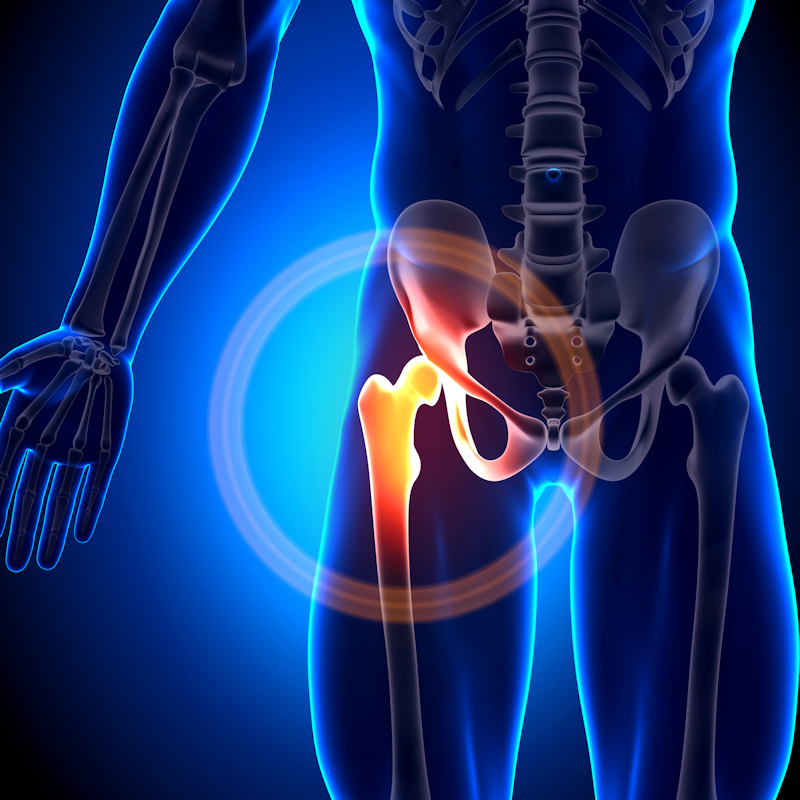

A deep-learning model that includes digital x-rays reconstructed from 3D hip CT images shows promise for predicting subsequent fractures in patients with a relatively recent hip break, researchers have found.

Patients who sustain an initial fracture are at highest risk for another over the next few years, the investigators explained. But models to predict short-term subsequent risk have not been developed. To fill this knowledge gap, Kim and colleagues developed and validated a deep-learning prediction model for subsequent fracture risk using digitally reconstructed x-rays from hip CT images in patients with recent hip fractures.

Their research included 1,480 adults who underwent 3D hip CT imaging prompted by a fracture between January 2004 and December 2020. Mean follow-up time was 3.4 years, and primary outcomes were subsequent bone fractures in the spine, hip, humerus, or wrist, occurring at least three months after the initial break. The team generated 2D frontal, lateral, and axial digitally reconstructed x-rays from the CT images, and used DenseNet convolutional neural network modules to estimate a patient's future fracture risk based on imaging features (this combination was dubbed the "ensemble model").